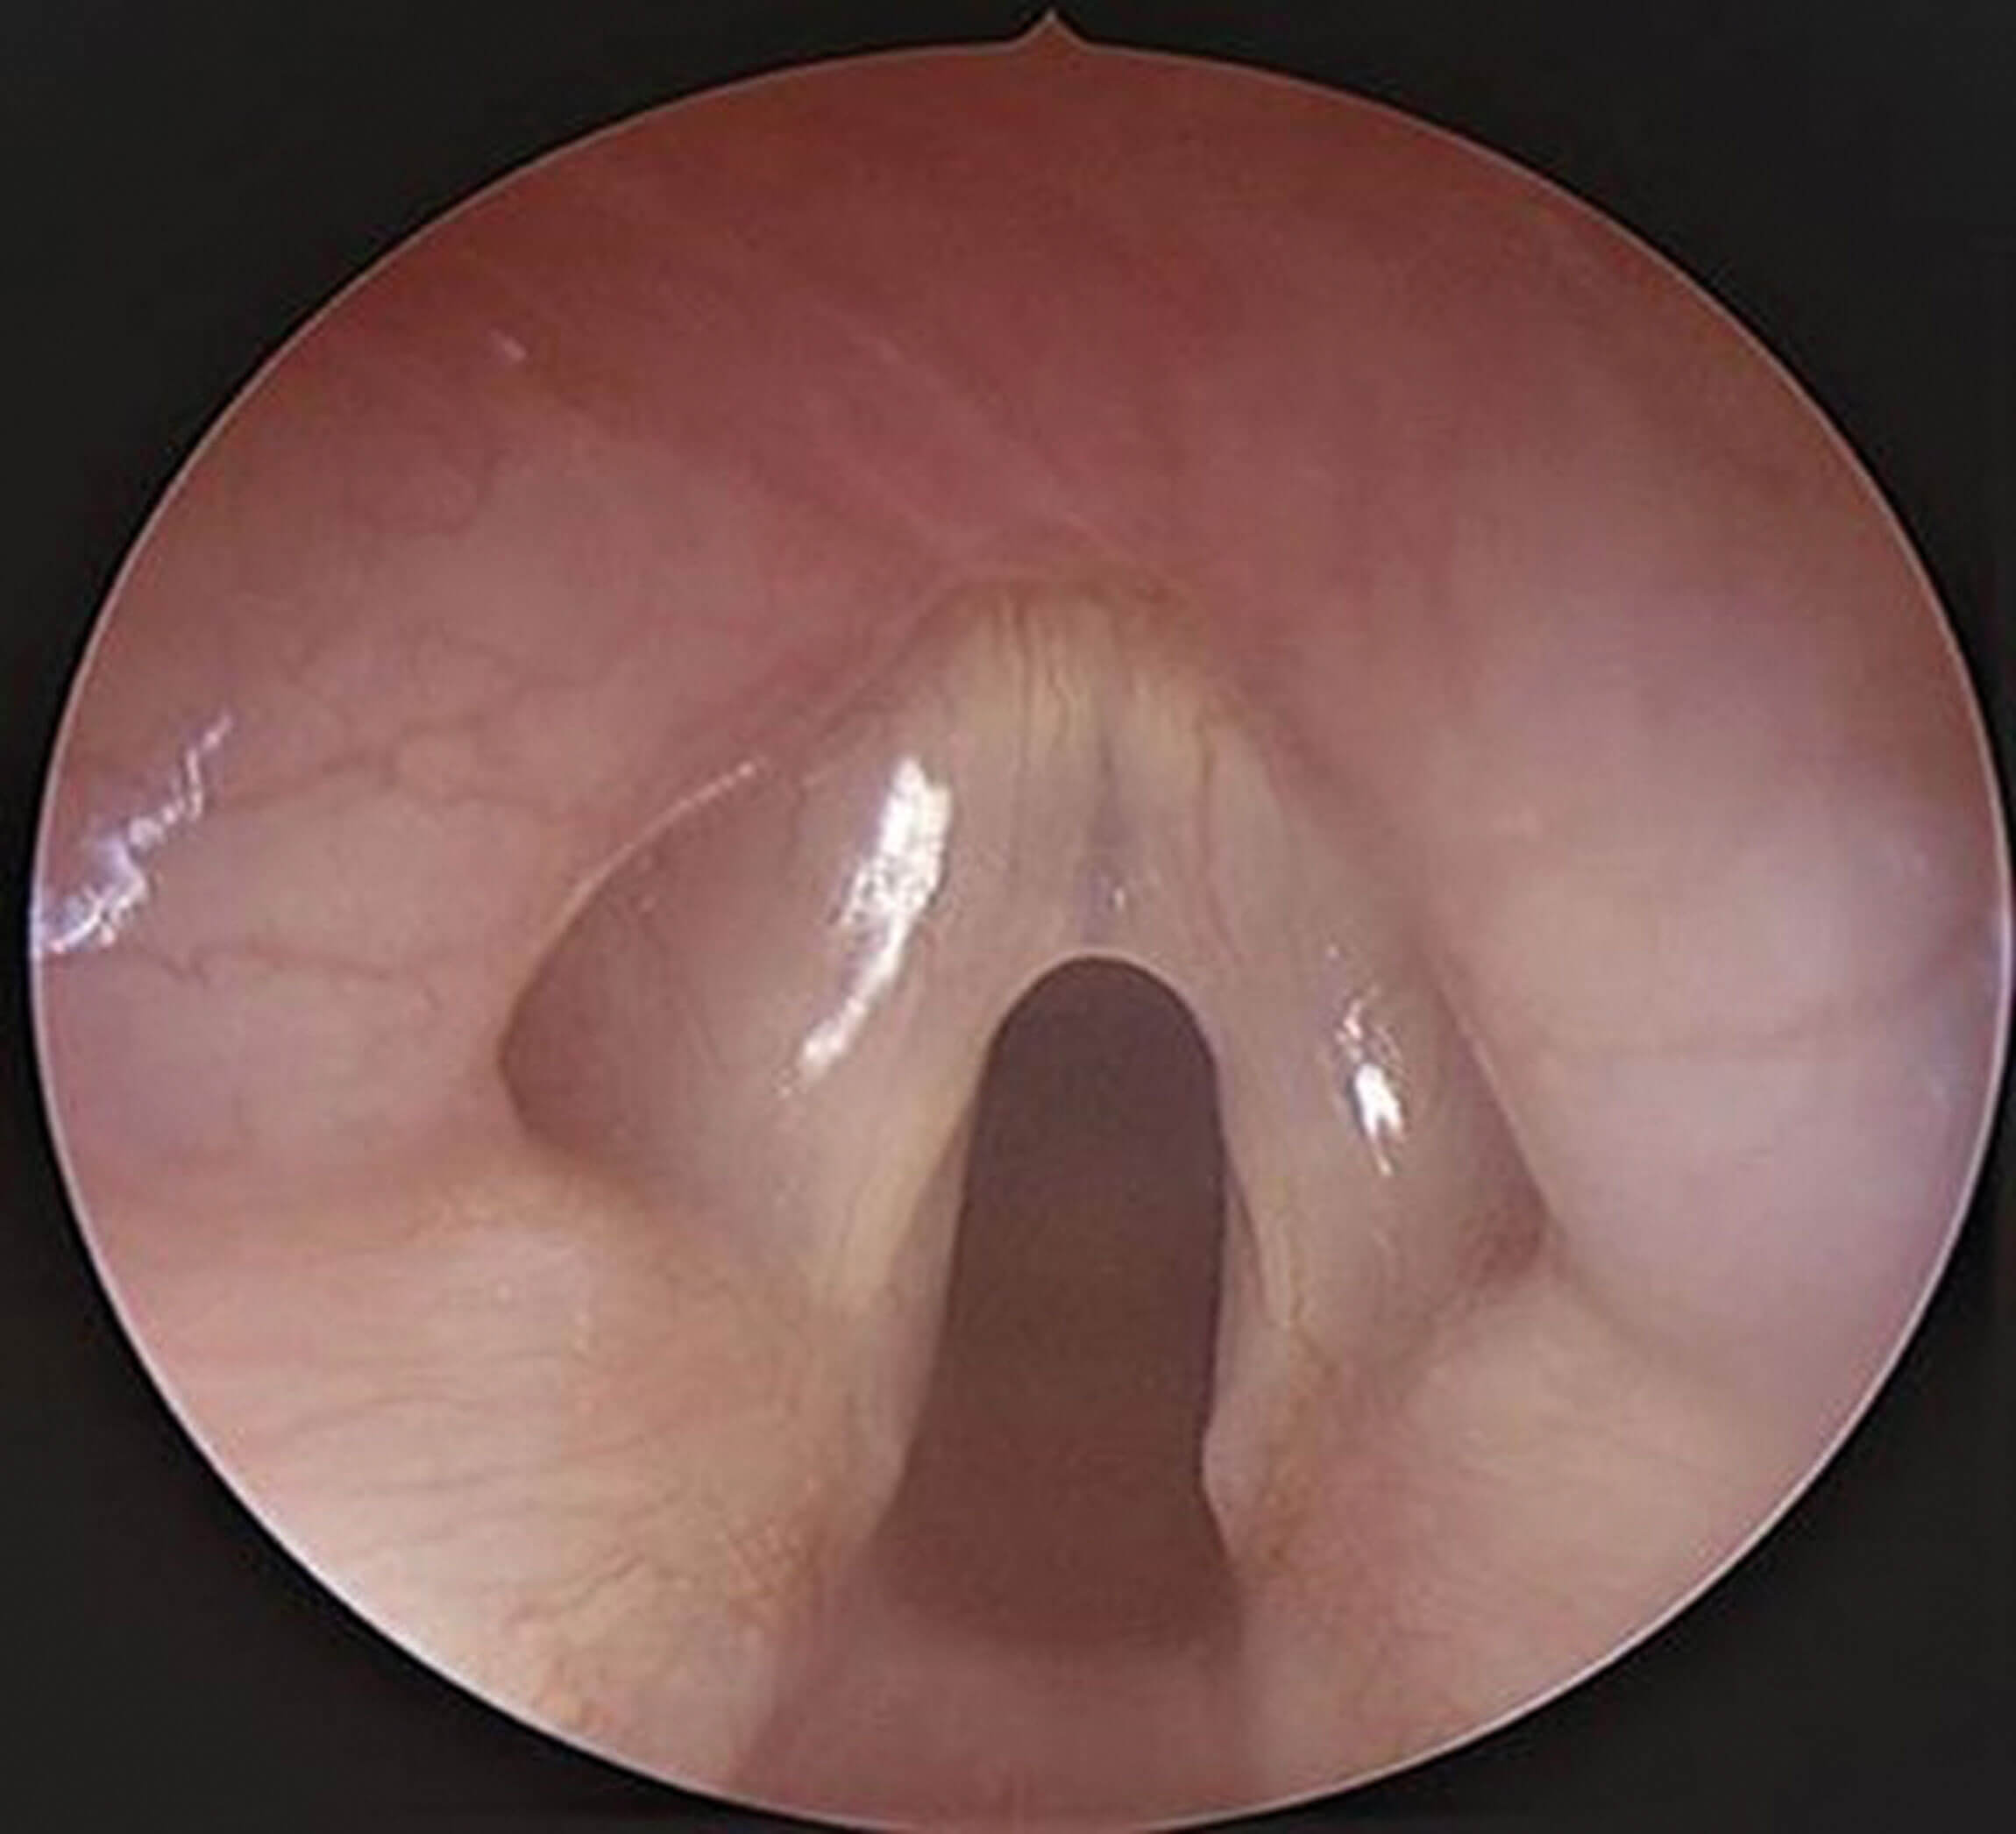

Figure 3. Endoscopic view of larynx showing a thin anterior glottic web.

Division of the web endoscopically (whether as a definitive treatment in itself or combined with open division and expansion of the subglottis) can be particularly accurate, allowing for precise division and visualisation of the vocal cord structures and anterior commissure. Thin webs (Figure 3) may be treated exclusively endoscopically with division of the web, balloon dilation and possible application of pharmacologic agents (Kenolog or Mitomycin C have been reported in the literature). Thicker webs usually require the insertion of a silastic ‘keel’ to act as a stent and this may also be inserted endoscopically or via a combined open and endoscopic procedure. Thicker webs associated with subglottic stenosis or an abnormal cricoid require open surgery with a thyroid alar cartilage or costal cartilage anterior graft.